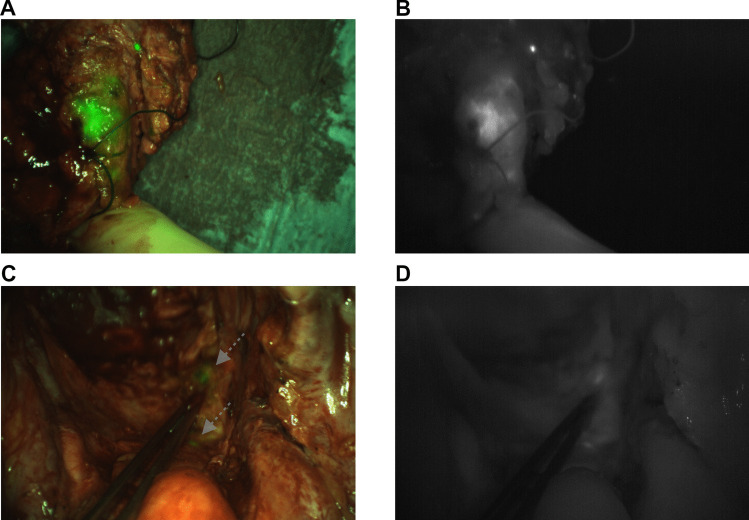

目的:在我们之前的2期试验中,局部晚期(LARC)或局部复发直肠癌(LRRC)患者接受了SGM-101,一种靶向cea的荧光剂,以实现实时近红外荧光(NIRF)引导手术。该研究表明,SGM-101能够在一些患者中进行额外的肿瘤切除,并支持其他患者进行微创手术。尽管术中有这种积极的效果,但对长期肿瘤控制的影响尚不清楚。因此,在这篇文章中,我们报告了所有参与试验的直肠癌患者的长期预后。程序:对参与SGM-101二期试验的所有29例LARC和LRRC患者收集随访数据。主要结局指标为5年局部肿瘤控制。结果:所有患者的中位随访时间为5.0年(IQR 4.5-5.5)。在12例LARC患者中,3例(25%)患者发生局部复发。在nif引导下进行微创手术的两例患者仍然没有局部复发。在17例接受根治性手术治疗的LRRC患者中,11例(65%)患者发生局部复发。在SGM-101引导手术直接导致R0而不是R1的3例患者中,1例患者出现局部复发(33%),而另外2例患者仍然没有局部复发。结论:这是第一个报道肿瘤靶向nif引导手术患者随访数据的研究。尽管SGM-101导致术中手术管理发生了必要的变化,但在整个队列中没有观察到改善的长期益处。然而,基于NIRF修改手术入路的患者子集-通过进行微创手术或切除额外的恶性组织-显示出良好的长期预后。正在进行的大型试验的结果正在等待中。

Purpose: In our previous phase 2 trial, patients with locally advanced (LARC) or locally recurrent rectal cancer (LRRC) received SGM-101, a CEA-targeted fluorescent agent, to enable real-time near-infrared fluorescence (NIRF) guided surgery. This study demonstrated that SGM-101 enabled additional tumor removal in some patients and supported less invasive surgery in others. Despite this positive intraoperative effect, the impact on long-term tumor control is unknown. Therefore, in this article we report the long-term outcomes of all rectal cancer patients that participated to the trial.